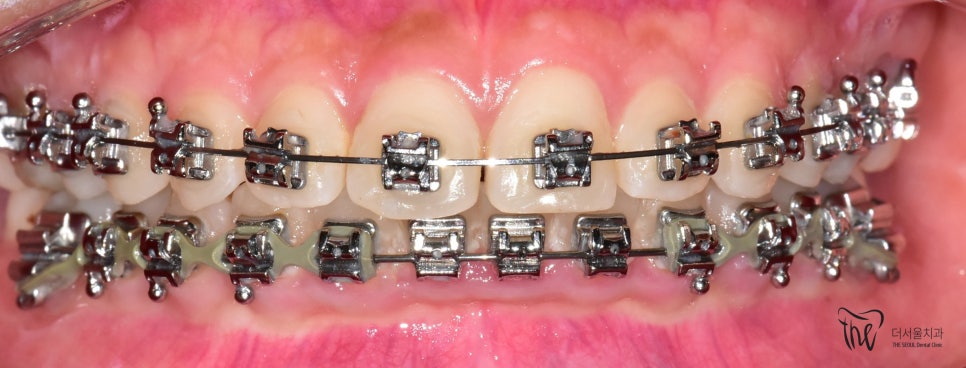

이 분은, 교정장치를 달고 있는 상태로 오셨는데

따라야 되는데 교합면 사진을 보게 되면

뭔가 전체 치열 자체는 고르게 느껴지죠?

근데, 이거 다 끝난게 아닙니다.

아직, 치아 얼라이먼트가 완성이 되지 않았습니다.

그러면서, 치아 레벨링이 완성이 되질 않았습니다.

레벨링 이라는 것은 위, 아래 치아들을 동시에

놓고 봤을 때의 가지런함을 뜻합니다.

치료 기간 2021.01.03 ~ 2022.08.14